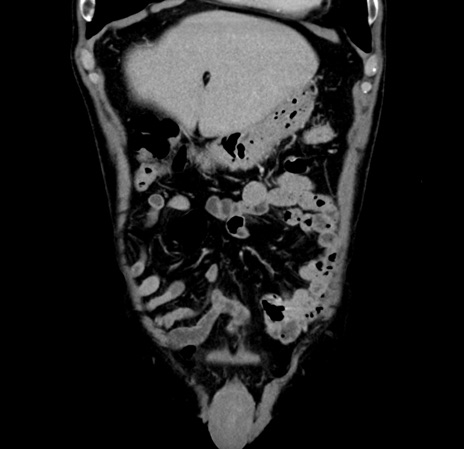

【腹部TIPS】症例70 CT(冠状断像)

【症例】60歳代 男性

とある所見でフォローされている。診断は?

CT

横断像